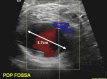

Coil embolization of an aberrant posterior tibial artery pseudoaneurysm after total knee arthroplasty

Arterial injury is a recognized but rare complication of total knee arthroplasty. These injuries, however, can be exceptionally devastating and potentially result in limb loss. Presentation may be delayed with symptoms associated with mass effect rather than with ischemia. We describe treatment of a patient with presentation delayed 2 weeks. In addition, the patient's arterial branch pattern demonstrated aberrant anatomy with high takeoff of the posterior tibial artery. This patient was successfully treated with transcatheter coil embolization. The current treatment options and published literature are reviewed.